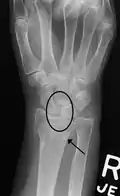

X-ray images indicate scapholunate ligament instability when the scapholunate distance is more than 3 mm, which is called scapholunate dissociation.[7] A static scapholunate instability is generally readily visible, but a dynamic scapholunate instability can only be seen radiographically in certain wrist positions or under certain loading conditions, such as when clenching the wrist, or loading the wrist in ulnar deviation.[6]

In order to diagnose a SLAC wrist you need a posterior anterior (PA) view X-ray, a lateral view X-ray and a fist view X-ray.[8] The fist X-ray is often made if there is no convincing Terry Thomas sign. A fist X-ray of a scapholunate ligament rupture will show a descending capitate bone. Making a fist will give pressure at the capitate, which will descend if there is a rupture in the scapholunate ligament.

Dynamic scapholunate instability visible upon clenching the wrist -